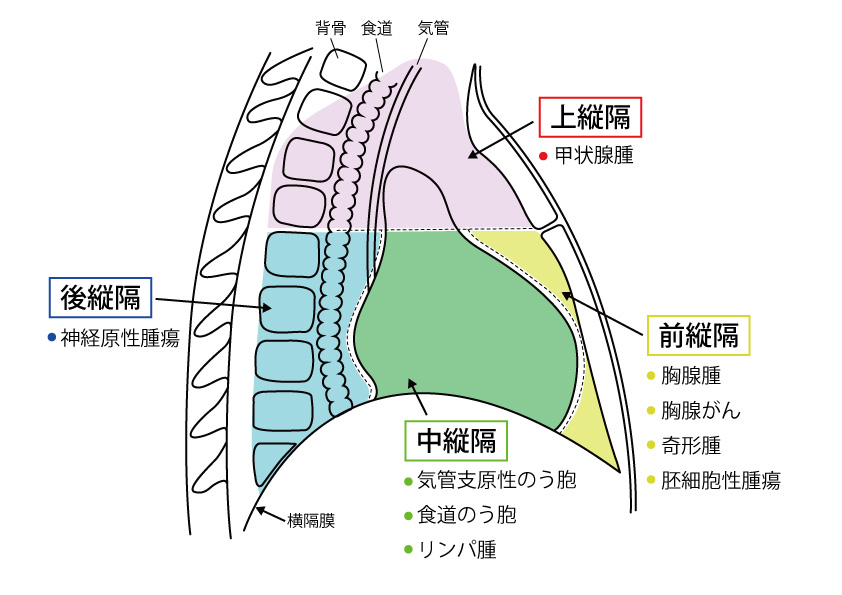

尿崩症 縦隔腫瘍 - Genspark, 縦隔腫瘍(じゅうかくしゅよう Mediastinal tumor) – 呼吸器疾患,

縦隔腫瘍(じゅうかくしゅよう Mediastinal tumor) – 呼吸器疾患, 尿崩症 縦隔腫瘍 - Genspark,

尿崩症 縦隔腫瘍 - Genspark, 頸胸部 CT の術後経過 : a )術前, b )術後 1 日目, c )術後22日,

頸胸部 CT の術後経過 : a )術前, b )術後 1 日目, c )術後22日, 胸部X線の正常・異常画像を見極める〜日常診療で出合う境界症例,

胸部X線の正常・異常画像を見極める〜日常診療で出合う境界症例, 112F47 | 医原性・化学物質による肺障害 国試 | テコプラ,

112F47 | 医原性・化学物質による肺障害 国試 | テコプラ, 一般撮影|大阪母子医療センター,

一般撮影|大阪母子医療センター, 胸腺腫(きょうせんしゅ Thymoma) – 呼吸器疾患 - 神戸きしだ,

胸腺腫(きょうせんしゅ Thymoma) – 呼吸器疾患 - 神戸きしだ, 一般撮影|大阪母子医療センター,

一般撮影|大阪母子医療センター, 中央放射線科|国民健康保険 小松市民病院,

中央放射線科|国民健康保険 小松市民病院, 稀少疾患先端医療センター - 東京科学大学病院 医科(医系診療部門),

稀少疾患先端医療センター - 東京科学大学病院 医科(医系診療部門), 尿崩症 縦隔腫瘍 - Genspark,